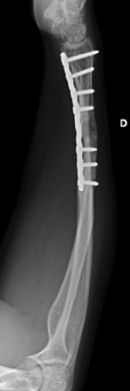

Las fracturas desplazadas o inestables precisarán de reducción cerrada o abierta en quirófano, asociado en algunos casos a osteosíntesis (Figura 10). Las fracturas localizadas en la unión metafiso-diafisaria distal son inestables y en muchos caos requieren tratamiento quirúrgico (Figura 11).

Figura 11: a, b-Fractura metafiso-diafisaria distal inestable. c, d-Control radiológico tras reducción donde se aprecia mala reducción. e, f-Síntesis mediante placa y tornillos.